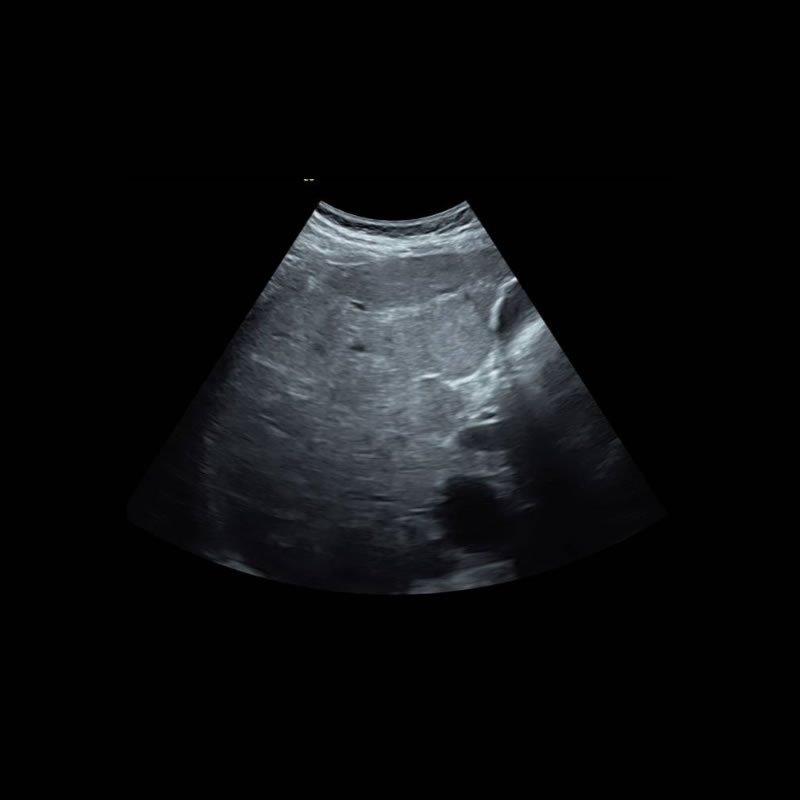

Paciente de 37 años, gestante, concurre a consulta obstétrica y se visualiza como hallazgo hepatomegalia y multiples nódulos hepáticos a partir del cual comienza a estudiarse.